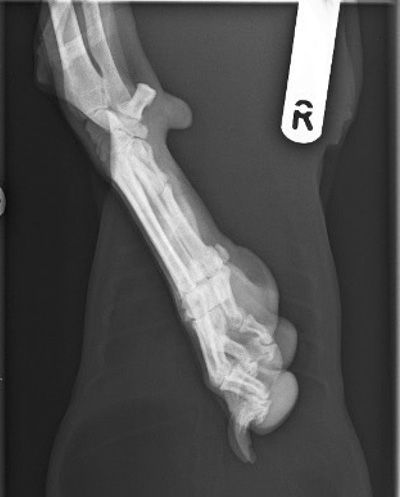

In DR systems, overexposure of radiographs often leads to saturation of the detector that reduces the ability of the pixels to differentiate grey tonal variation and can lead to a flat, poor contrast image and, in extreme cases, visualisation of the calibration mask of the detector (Figure 1). It should also be remembered that the photostimulable phosphors (PSP) of CR systems are very prone to backscatter and, if high exposures are used, will result in grey, flat images (Figure 2). The PSP plates of the CR system also need to be erased prior to any exposure and may require a double erasure if high exposure factors have been used to reduce poor contrast images and the risk of ghost images being present (Figure 3).

Figure 3. Mediolateral view of the right carpus and pes (CR image): a silhouette of the previous image – a DV thorax and cranial abdomen is visible with distal right forelimb superimposed. This is due to inadequate erasure of the PSP plate and residual ghosting of the thoracic image remains.